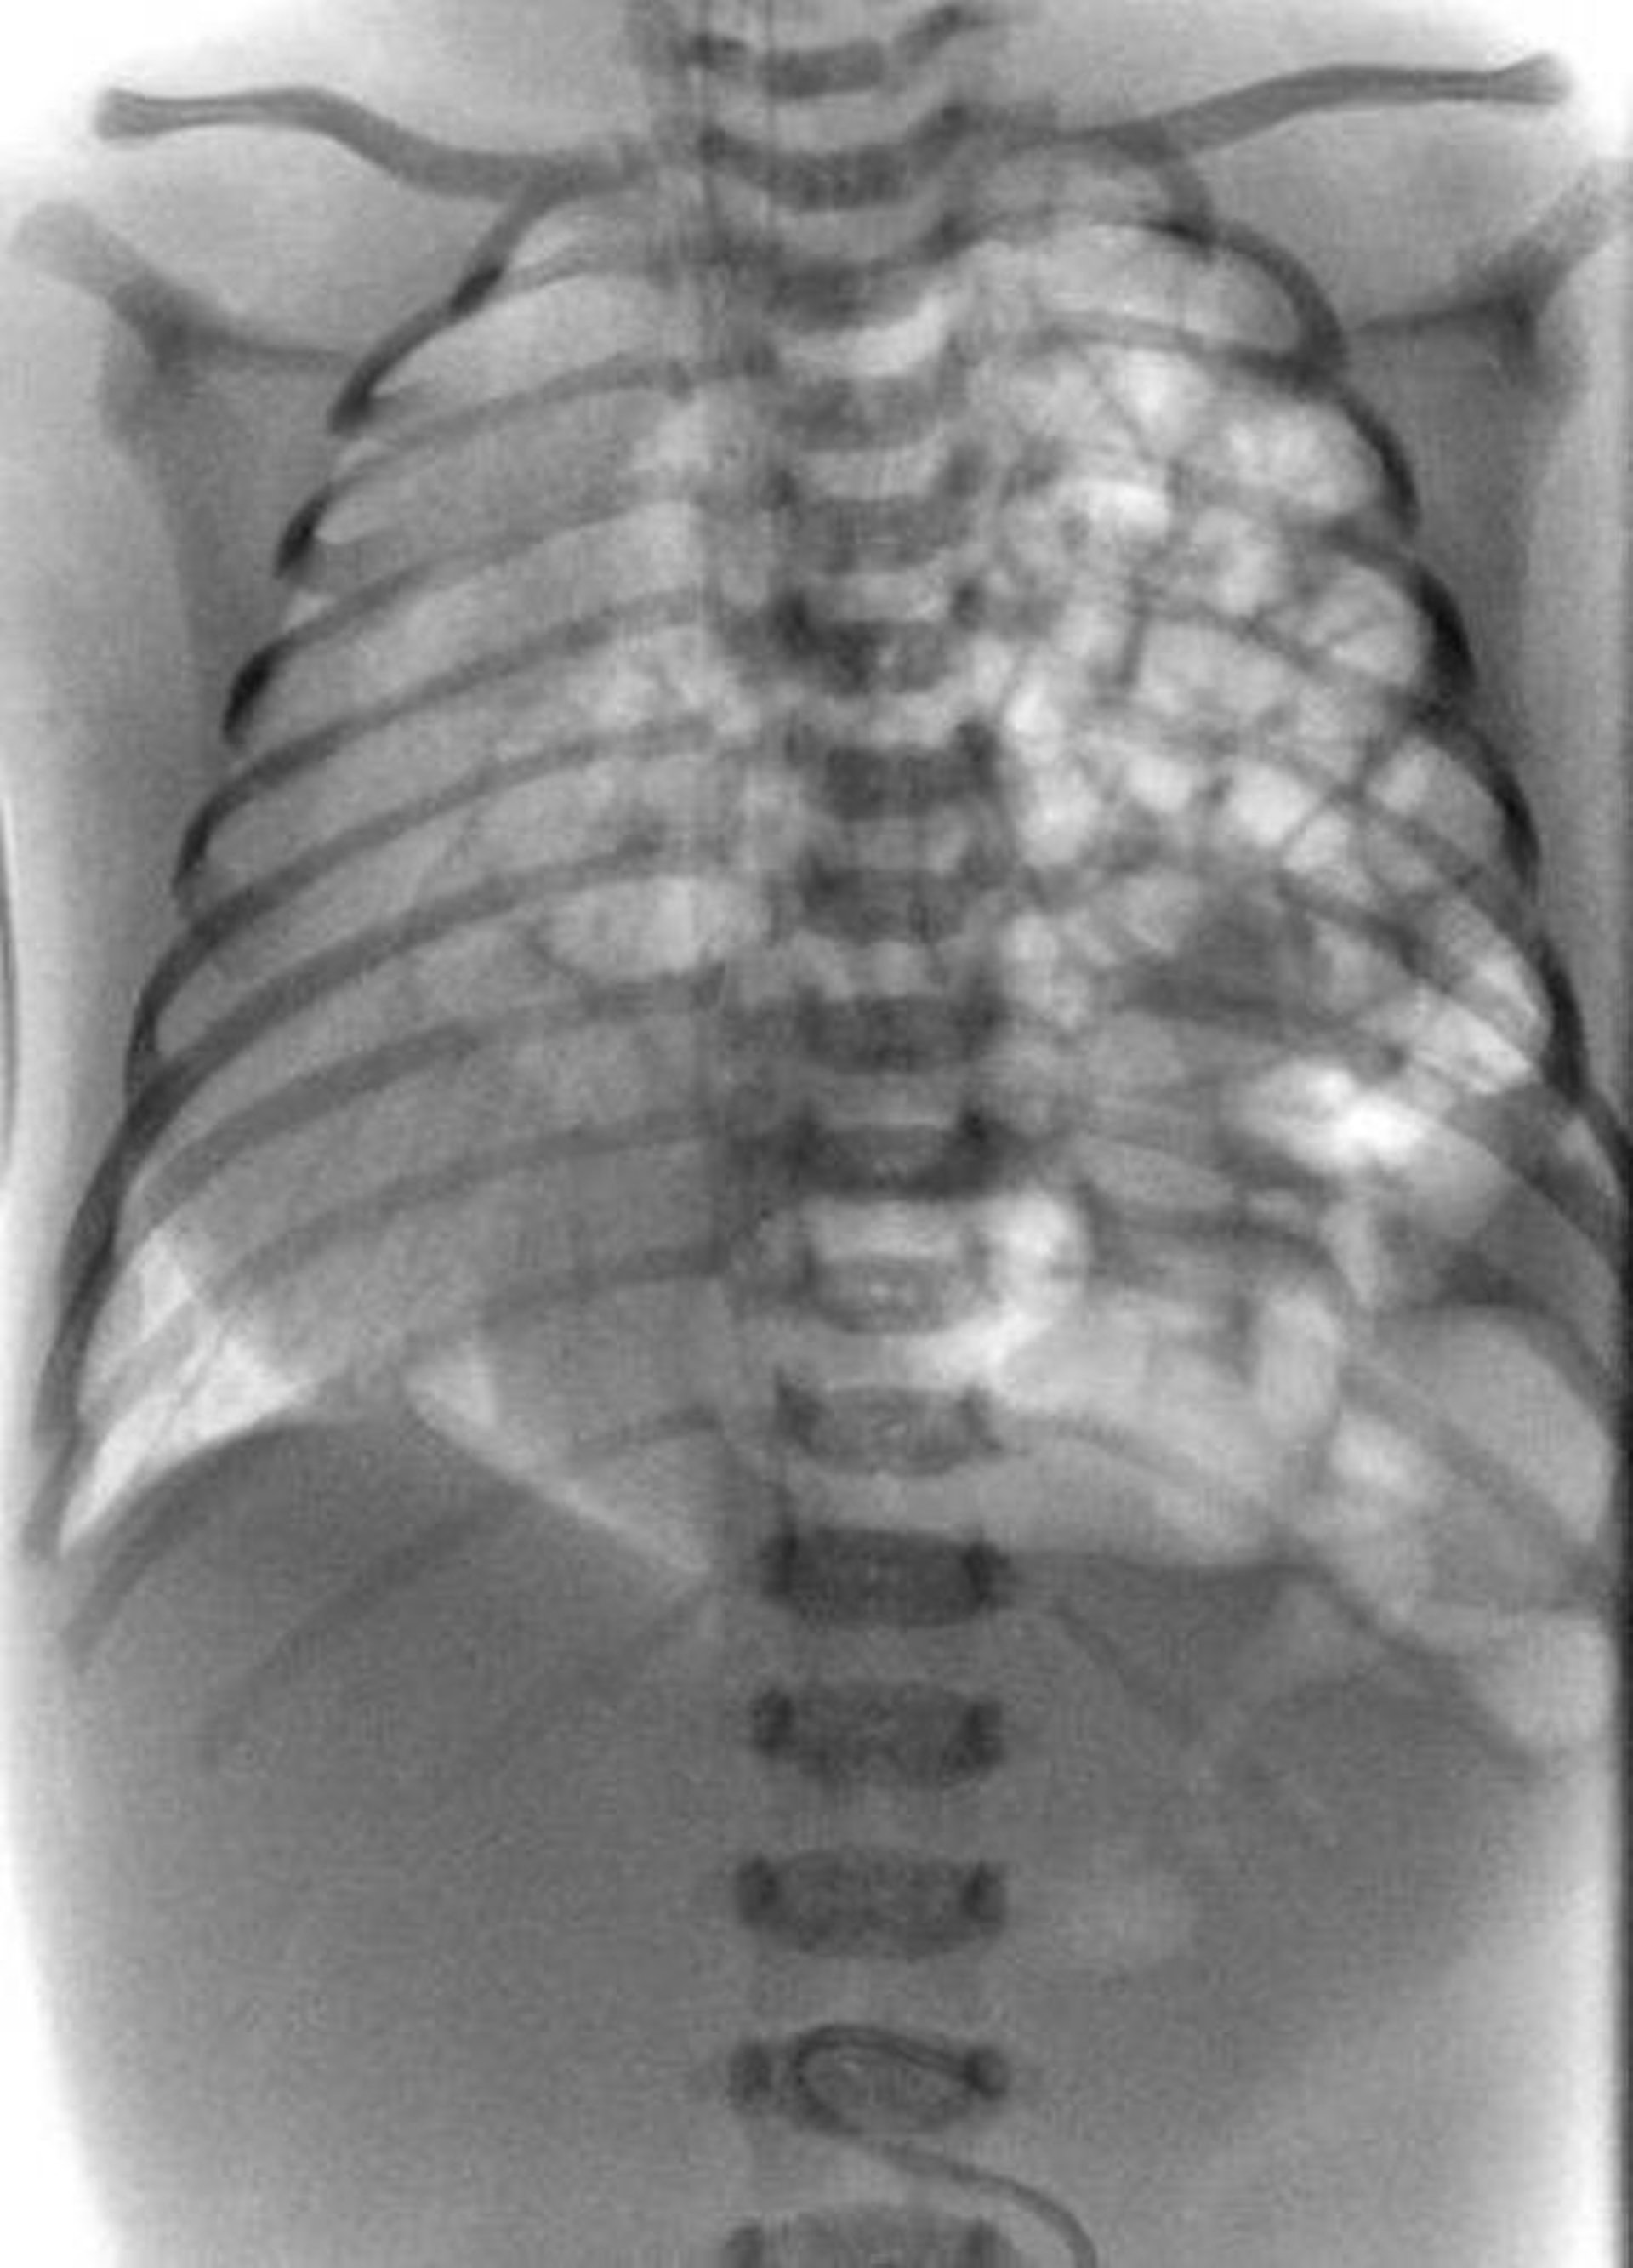

Questa RX mostra un'ernia diaframmatica congenita in un neonato. L'intestino (il groviglio bianco) sporge nel torace a sinistra (lato destro della radiografia).

DU CANE MEDICAL IMAGING LTD/SCIENCE PHOTO LIBRARY